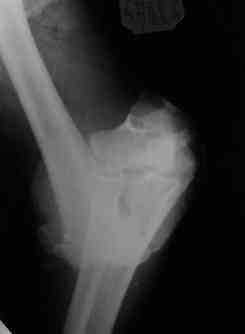

Открытый чрезмыщелковый перелом плеча |

Уважаемые коллеги! Мужчина, 49 лет, упал 2 недели назад, будучи около полугода в запое. Сразу припоступлении рана промыта а-ля пульсирующая струя" до 8 литров и стабилизация (без ушивания раны). Через 2 дня пациент покинул отделение, думаю, что сражался с рогатыми животными, еще через 4 дня победив всех врагов пришел как путный с поникшей головой. На настоящий момент рана с обильным гнойным отделяемым в виде комков, но повязка стала промокать меньше, температура субфебрильная 4 дня и выше 37,3 не поднималась, боли умеренные, больше ночью. Есть несколько вопросов: 1.Нужна ли сейчас ревизия и дебридмент? 2.Оптимальный вариант дренирования? (сейчас просто резиновые выпускники, в т.ч. через онтраппертуру). 3.Нижний стержень находиться в очаге. Его необходимо убрать? Если да, то вариант фиксации.Жалко свою работу. Может общими усилиями спасем? ;) Спасибо. С уважением, Алексей.

Уважаемые коллеги. Внешний вид конечности через 5 недель после травмы. Рана гранулирует, отделяемое скудное. Прошу строго не судить за внешний вид АВФ: ну нет пока у нас параллельных зажимов (приходиться выкручиваться).